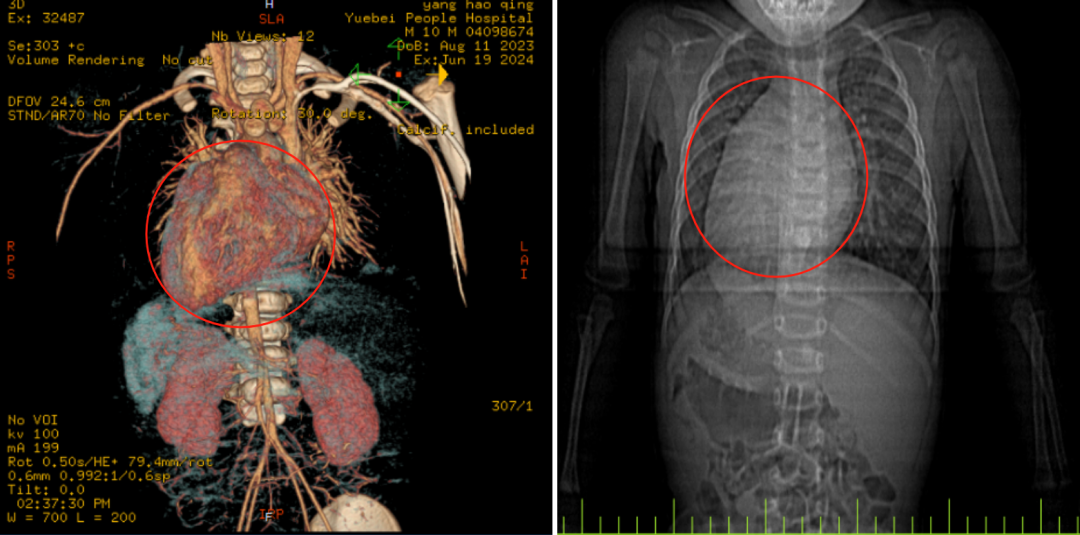

患儿胸腹主动脉CTA提示:腹腔脏器转位,心脏位于身体右侧